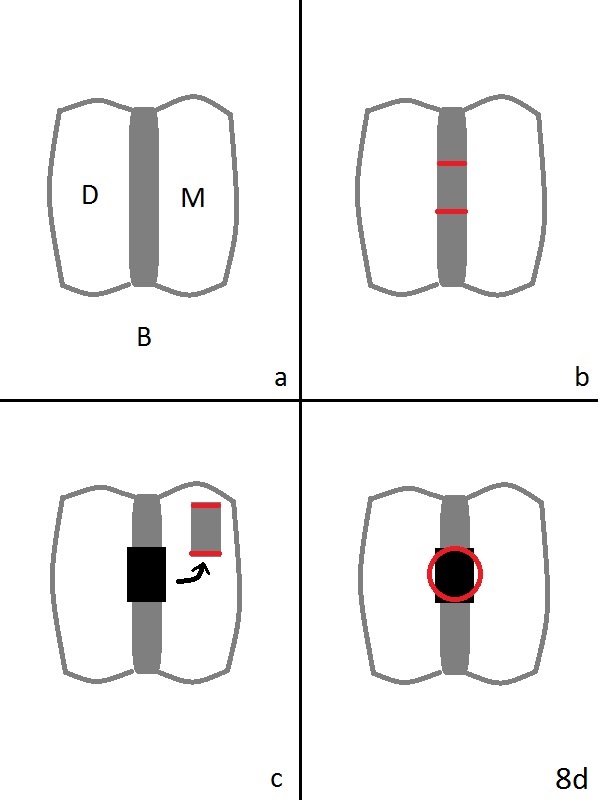

A 43-year-old man has residual roots at #30 (Fig.1). The mesial (M) and distal (D) roots approximates each other so close that the septum is thin (Fig.1,3-5). The latter is unfavorable for osteotomy. After extraction (Fig.5), the middle of the septum (Fig.8a (axial section of the sockets)) will be sectioned (Fig.6, 8b,c) prior to initial osteotomy (Fig.7,8d). The depth of the latter will be ~ 5 mm (Fig.2 red line) for a 13 mm (pink line) IBS implant.